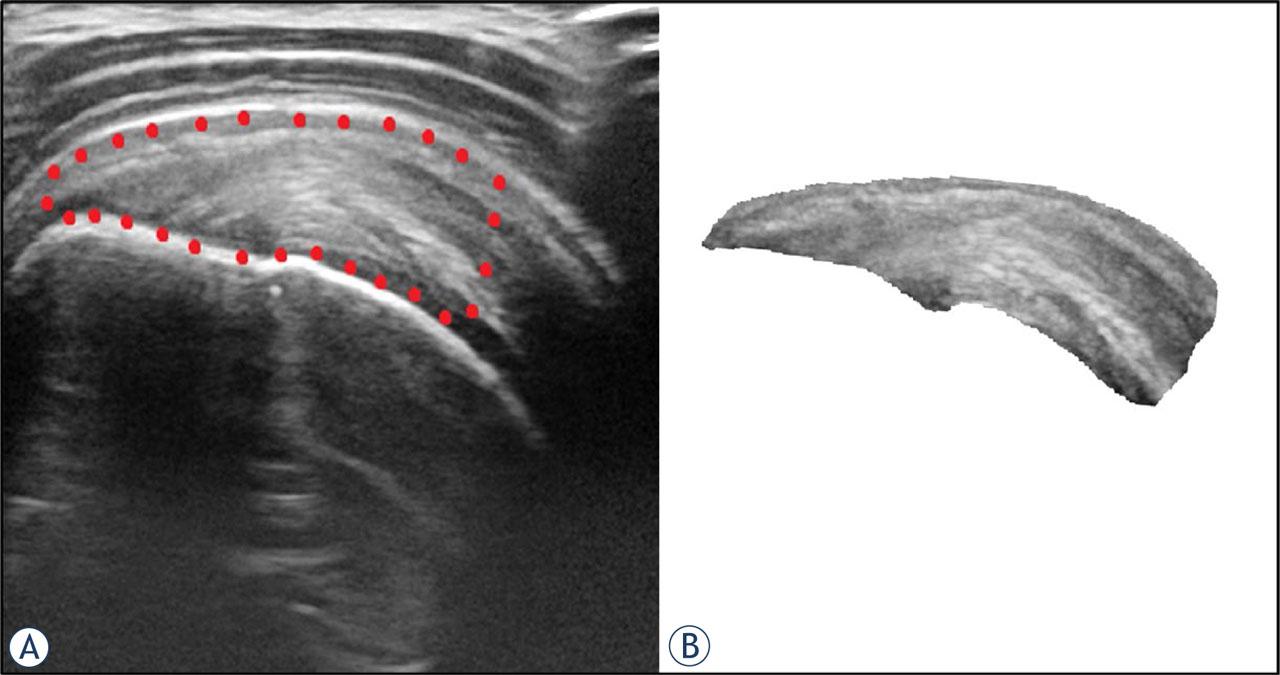

FIGURE 1.